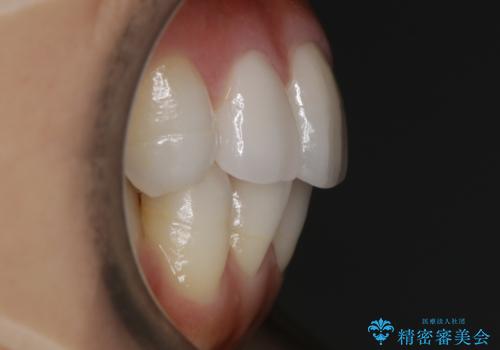

【非抜歯】噛み合わせを整えたい! インビザライン矯正

- 嚙み合わせのズレを主訴にご来院されました。

前歯・奥歯ともにセラミッククラウンで治療されている歯があったため、その歯にあまり影響が出ない範囲内で全体の噛み合わせが良くなるような動きを組み込んで治療を進めることとなりました。

被せ物がある場合

矯正治療前にセラミック等の被せ物をされている場合、それ自体の外形は矯正治療では変更することができないため、その他の天然歯の移動に影響を与えてしまう場合があります。また、治療上設定されるアタッチメント(歯の表面に付けるプラスチックの突起)が付かない場合が多く、歯のコントロールが不足する場合があります。